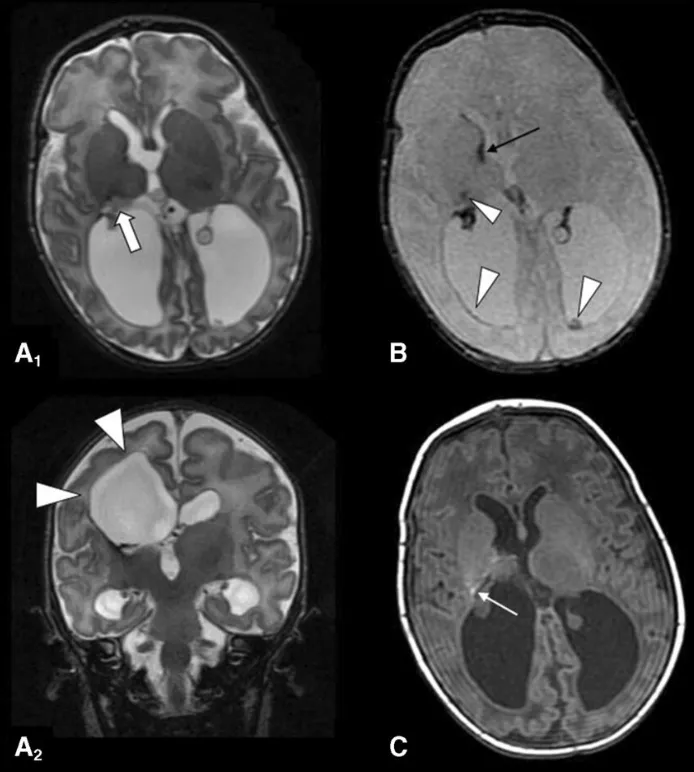

图1:出生后第10天采集的MRI检查结果,影像表现符合Papile III级生发基质出血及脑室周围白质软化的特征。轴位与冠状位T2加权涡轮自旋回波图像显示侧脑室扩张,右侧脑室周围、内囊后肢及丘脑区域可见软化性改变;T2*加权序列在丘脑-尾状核沟水平、内囊后肢及脑室壁可见出血后含铁血黄素沉积;T1加权图像在内囊后肢层面亦可识别微小的正铁血红蛋白沉积。

图3:术后MRI随访显示右侧岛周功能断联手术区域的结构变化,图中标注了岛周夹层的范围以及上颞回、中颞回切除后的影像改变,箭头指示内囊离断延伸至侧脑室房部。